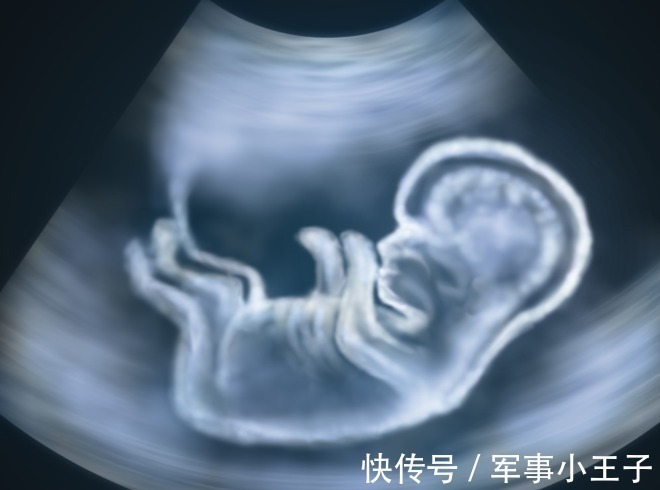

2、心室内的微小钙化灶

什么是心室内的微小钙化灶?

这个在孕检指标里面显示的词是:胎儿心室内点状回声。

发生率:1.5%-4%,亚洲女性发生率更高。

左心室:88%,右心室:5%,左右心室:7%。

当你的大排畸报告显示有心室内点状回声,不用太担心,因为95%在孕晚期都会消失。

尤其是,如果只是左心室有,右心室没有,更不需要担心。大多数左心室内点状强回声会随孕周增加而缩小,回声强度也逐渐减弱,到足月妊娠几乎完全消失。

如果左右心室都有,尤其是≥35岁的准妈妈,或合并其他高危因素,存在其他明显的结构或软指标异常,需要做胎儿染色体核型检查及进一步产前咨询与动态随访。